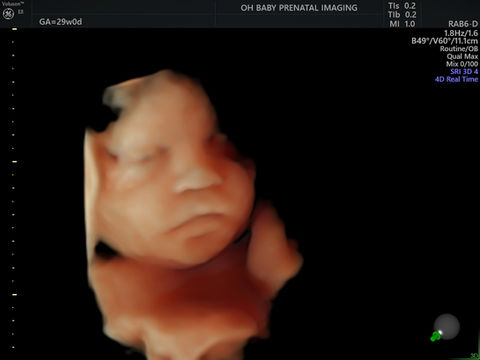

4D Gallery